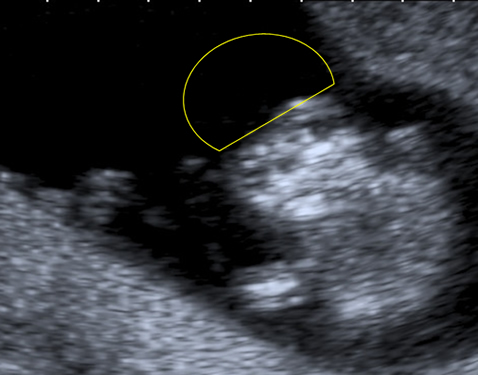

The anencephalic fetus demonstrates no clear frontal bone and often the facial bones may appear unusual also with the orbits appearing prominent – the so called 'frog-eyed appearance'. There may be some brain visible but this is variable. There is no bright skull vault covering the brain.

This image shows the facial view of an anencephalic fetus. Note the frog-eyed appearance. Also note that the skull vault is completely absent.